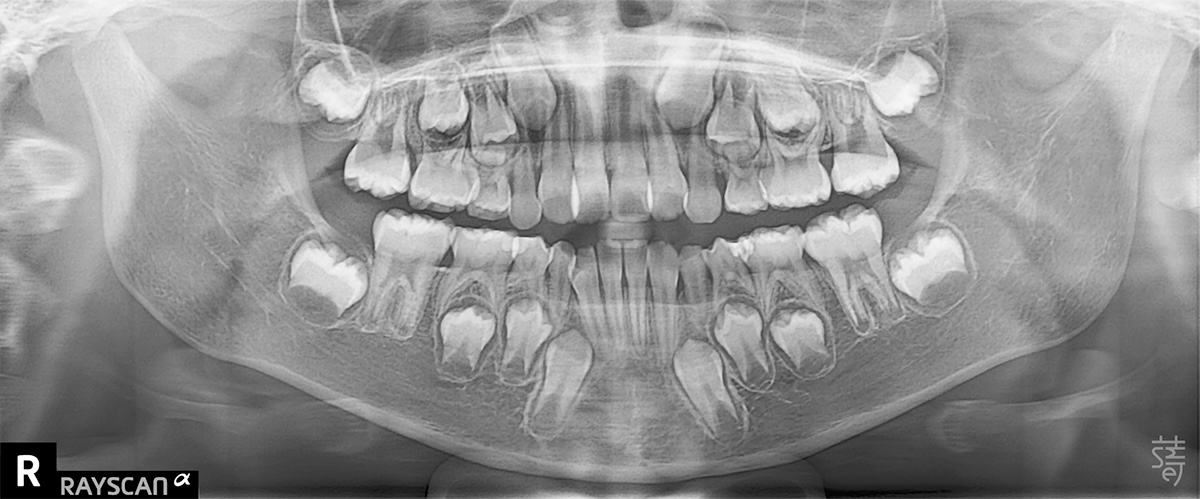

檢查後發現,小緹的牙弓偏窄、牙齒擁擠,門牙稍往前,加上她習慣用錯誤的方式呼吸,這些都會讓狀況逐漸惡化。

Dr. Ko found that Ti’s dental arch was narrow, her front teeth slightly protruded, and her breathing habits weren’t helping—issues that would likely worsen over time.

不過柯醫師也向媽媽解釋,這類狀況在齒列混合期孩子身上很常見,小緹正處在「第一階段矯正期」,也就是7~10 歲、乳牙和恆牙同時存在的階段。這時顎骨正快速發育,是早期介入的黃金時間,只要妥善接受治療,不僅能引導恆牙長在較理想的位置,也能降低未來需要大規模矯正的可能。

He explained that this is common in the mixed-dentition stage, when ages 7 to 10 offer a rare window: the jaw is still developing, and early orthodontic guidance can shape where adult teeth erupt and reduce the need for major treatment later on.

醫師提醒,適不適合兒童隱適美不是只單看年紀,而要看口腔內的四個牙區是否都處於混合齒列期(也就是乳牙和恆牙一起存在的階段)。

醫師會仔細評估牙齒萌出、咬合、發育狀態,才能確定是否適合使用。 這個評估過程,就像是替孩子做一次口腔發育健檢,確保每一步都安全又有效。

Age alone doesn’t determine whether a child is ready for Invisalign First. Orthodontists look at all four quadrants of the mouth to see if they’re in the mixed-dentition stage, when baby teeth and adult teeth are present at the same time.

They carefully assess how the teeth are erupting, how the bite fits, and how the jaws are growing before deciding if this approach is appropriate. In many ways, it’s like a full developmental checkup for the mouth—designed to make sure every step of treatment is both safe and truly helpful.